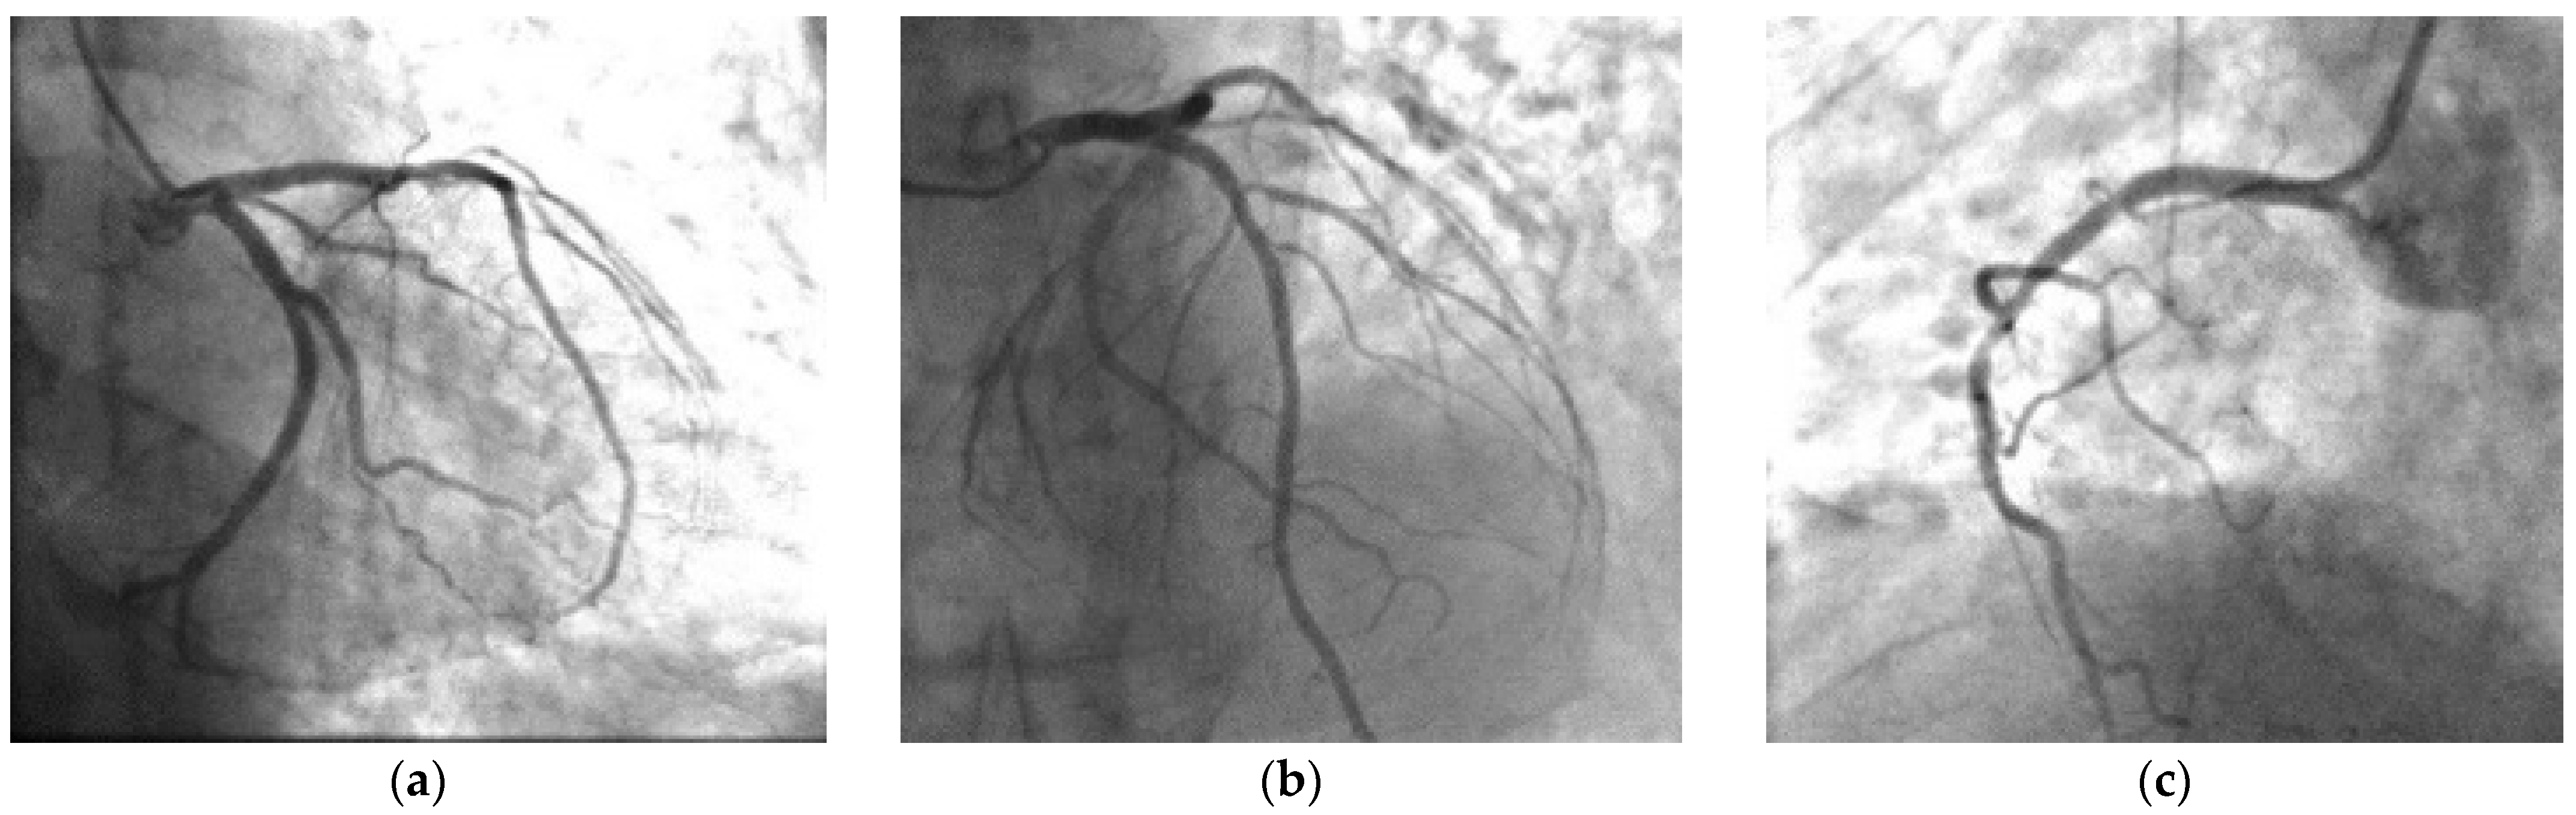

2. Case Presentation

3.5. Management of 5-FU Acute Coronary Syndrome with ST Segment Elevation

| CATH | Normal coronaries, ergonovine test + for spasm | No changes in comparison with the previous angiography | Normal coronaries | Normal coronaries, cold pressor test + for spasm | Severe multivessel coronary artery disease, cold pressor test | Normal coronaries | Generally reduced coronary flow. after 2 days normal coronaries. |